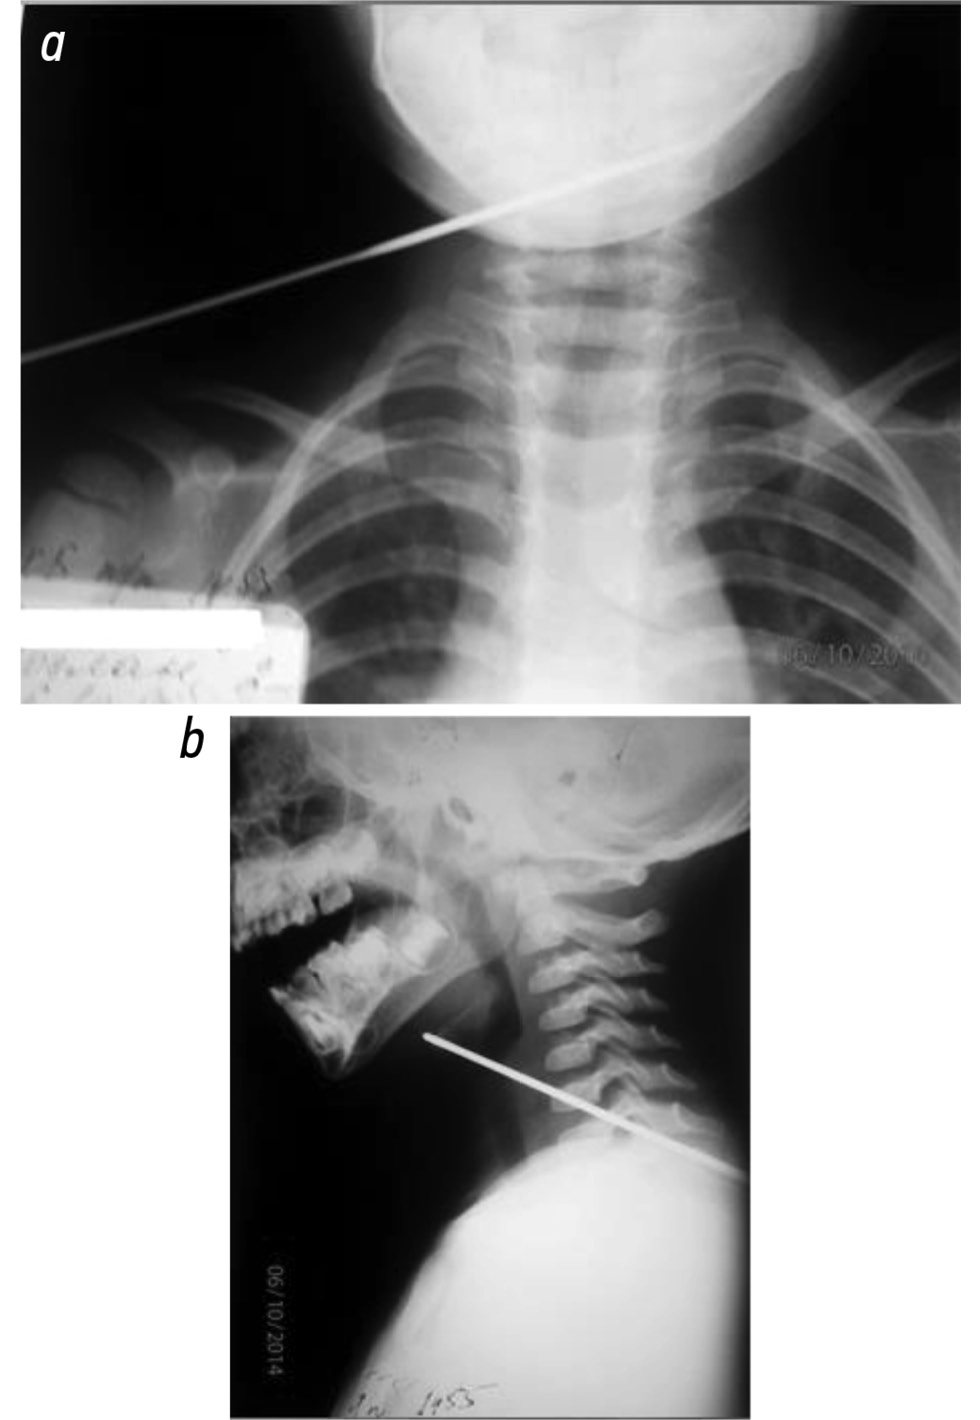

Больной Ю., 16 лет 10 мес., поступил в хирургическое отделение РДКБ с жалобами на боли в шее, гиперсаливацию, вынужденное положение головы и невозможность проглотить пищу. Мальчик чистил кариозный зуб швейной иглой и случайно вдохнул её. Больной обратился к хирургу по месту жительства и после рентгенографии грудной клетки был направлен в РДКБ с диагнозом «инородное тело пищевода» (рис. 5).

Рис. 5. Обзорная рентгенограмма шеи в прямой и боковой проекции: на уровне СIII–СIV определяется тень инородного тела — швейной иглы (a — прямая, b — боковая проекция).

Fig. 5. Plain X-ray of the neck in frontal and lateral projections: at the СIII–СIV level one can see the foreign body shadow — a sewing needle (a — direct projection, b — lateral projection).

Обзорная рентгенограмма шейного отдела позвоночника в прямой и боковой проекциях: на уровне СIII–СIV определяется тень инородного тела — швейная игла (см. рис. 5).